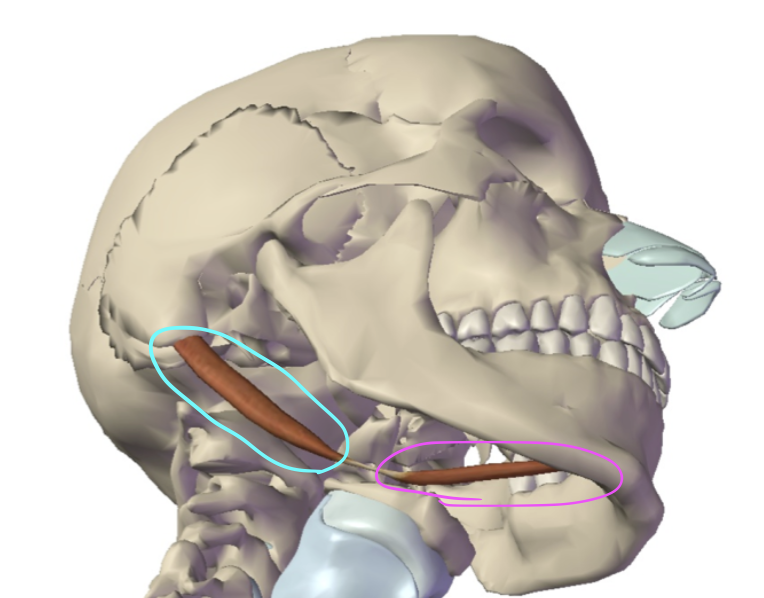

What is this muscle circled in pink?

Anterior digastric (hyoid up and forward)

What is this muscle circled in teal?

Posterior digastric (hyoid up and back)